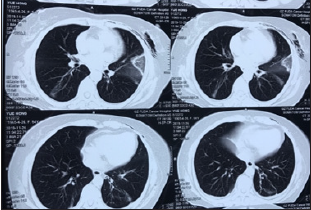

A female patient, aged 56, discovered multiple bilateral nodules in her lungs in October 2019. The patient underwent a percutaneous cryoablation procedure in November 2019 at a local hospital in Guongdong city to manage three of her multiple nodules, which showed a high risk of malignancy according to the radiographic presentation, in which a nodule of 7mm in diameter was located at the right upper lobe, another nodule of 7mm in diameter was located in the left upper lobe, and another nodule of 6mm in diameter was located at the left lower lobe. The patient then went for a routine CT follow-up in June 2020, and the radiographic imaging indicated ablated lesions marked by poor tissue healing with significant exudative infiltration at all three ablation zones with the presence of multiple ground-glass nodules and mixed ground-glass nodules as shown in Figure 1 & 2.

Figure 1: Ablated lesions was observed on the right upper lobe and left upper lobe of the lungs.

Figure 2:Remaining volume at risk.